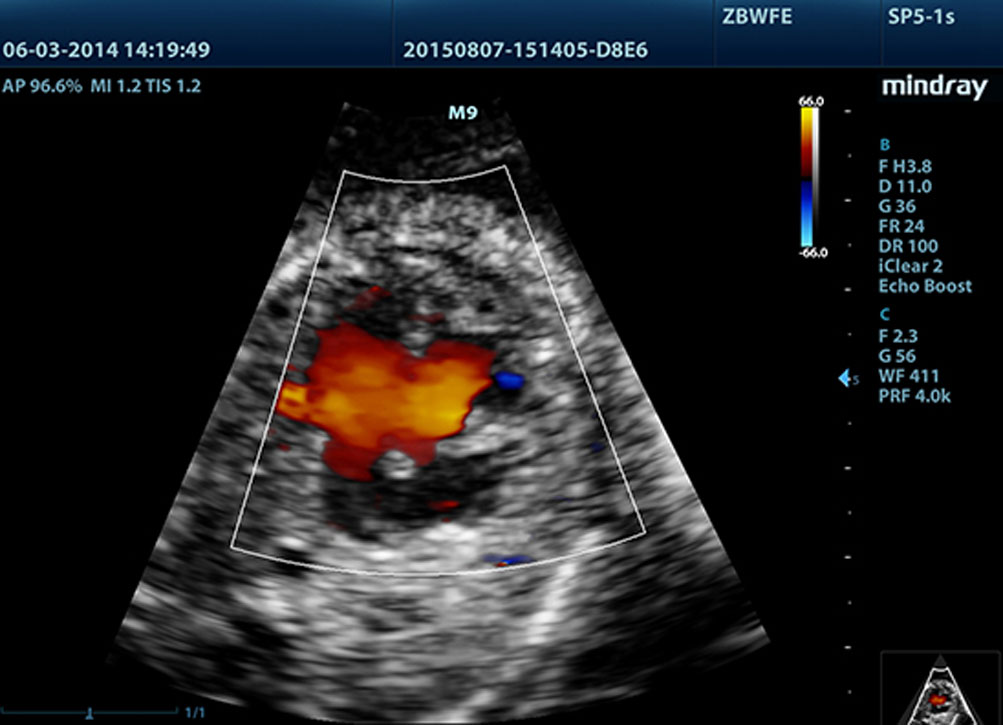

Proporcionando imĂĄgenes mĂĄs nĂtidas, todas las sondas compatibles con el M9 vienen equipadas con la tecnologĂa de transductor 3T Ășnica de Mindray. Mejorado con el a?adido de la tecnologĂa de cristal Ășnico, el M9 ofrece una mejor penetraciĂłn y flujo dinĂĄmico de color, especialmente durante escaneado de pacientes difĂciles.

LVO con ecocardiografĂa de estrĂ©s

Las capacidades superiores del M9 permiten la opacificaciĂłn LV durante el estrĂ©s, lo que mejora la discriminaciĂłn entre tejidos miocardiacos y coĂĄgulos de sangre y proporciona una mejor visualizaciĂłn de la superficie endocardiaca. La funciĂłn de ecocardiografĂa de estrĂ©s del M9 incluye un paquete completo para ecocardiograma de estrĂ©s farmacolĂłgico y de ejercicio. El paquete estĂĄ soportado por un sistema de informe flexible que puede ser optimizado para sus necesidades individuales.